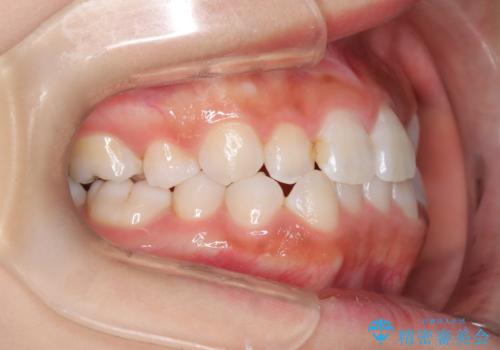

- 子供のころに矯正治療をされていたが、後戻りをしてしまったという20代女性の患者様です。上顎左右の2番が、咬合時に下顎の歯よりも内側に入っているクロスバイトという状態でした。奥歯の咬合関係は変えずに、マウスピース矯正にて前歯の並びを綺麗なアーチに仕上げました。再度後戻りしてしまうリスクを軽減させるために、リテーナー(保定装置)をお渡ししています。